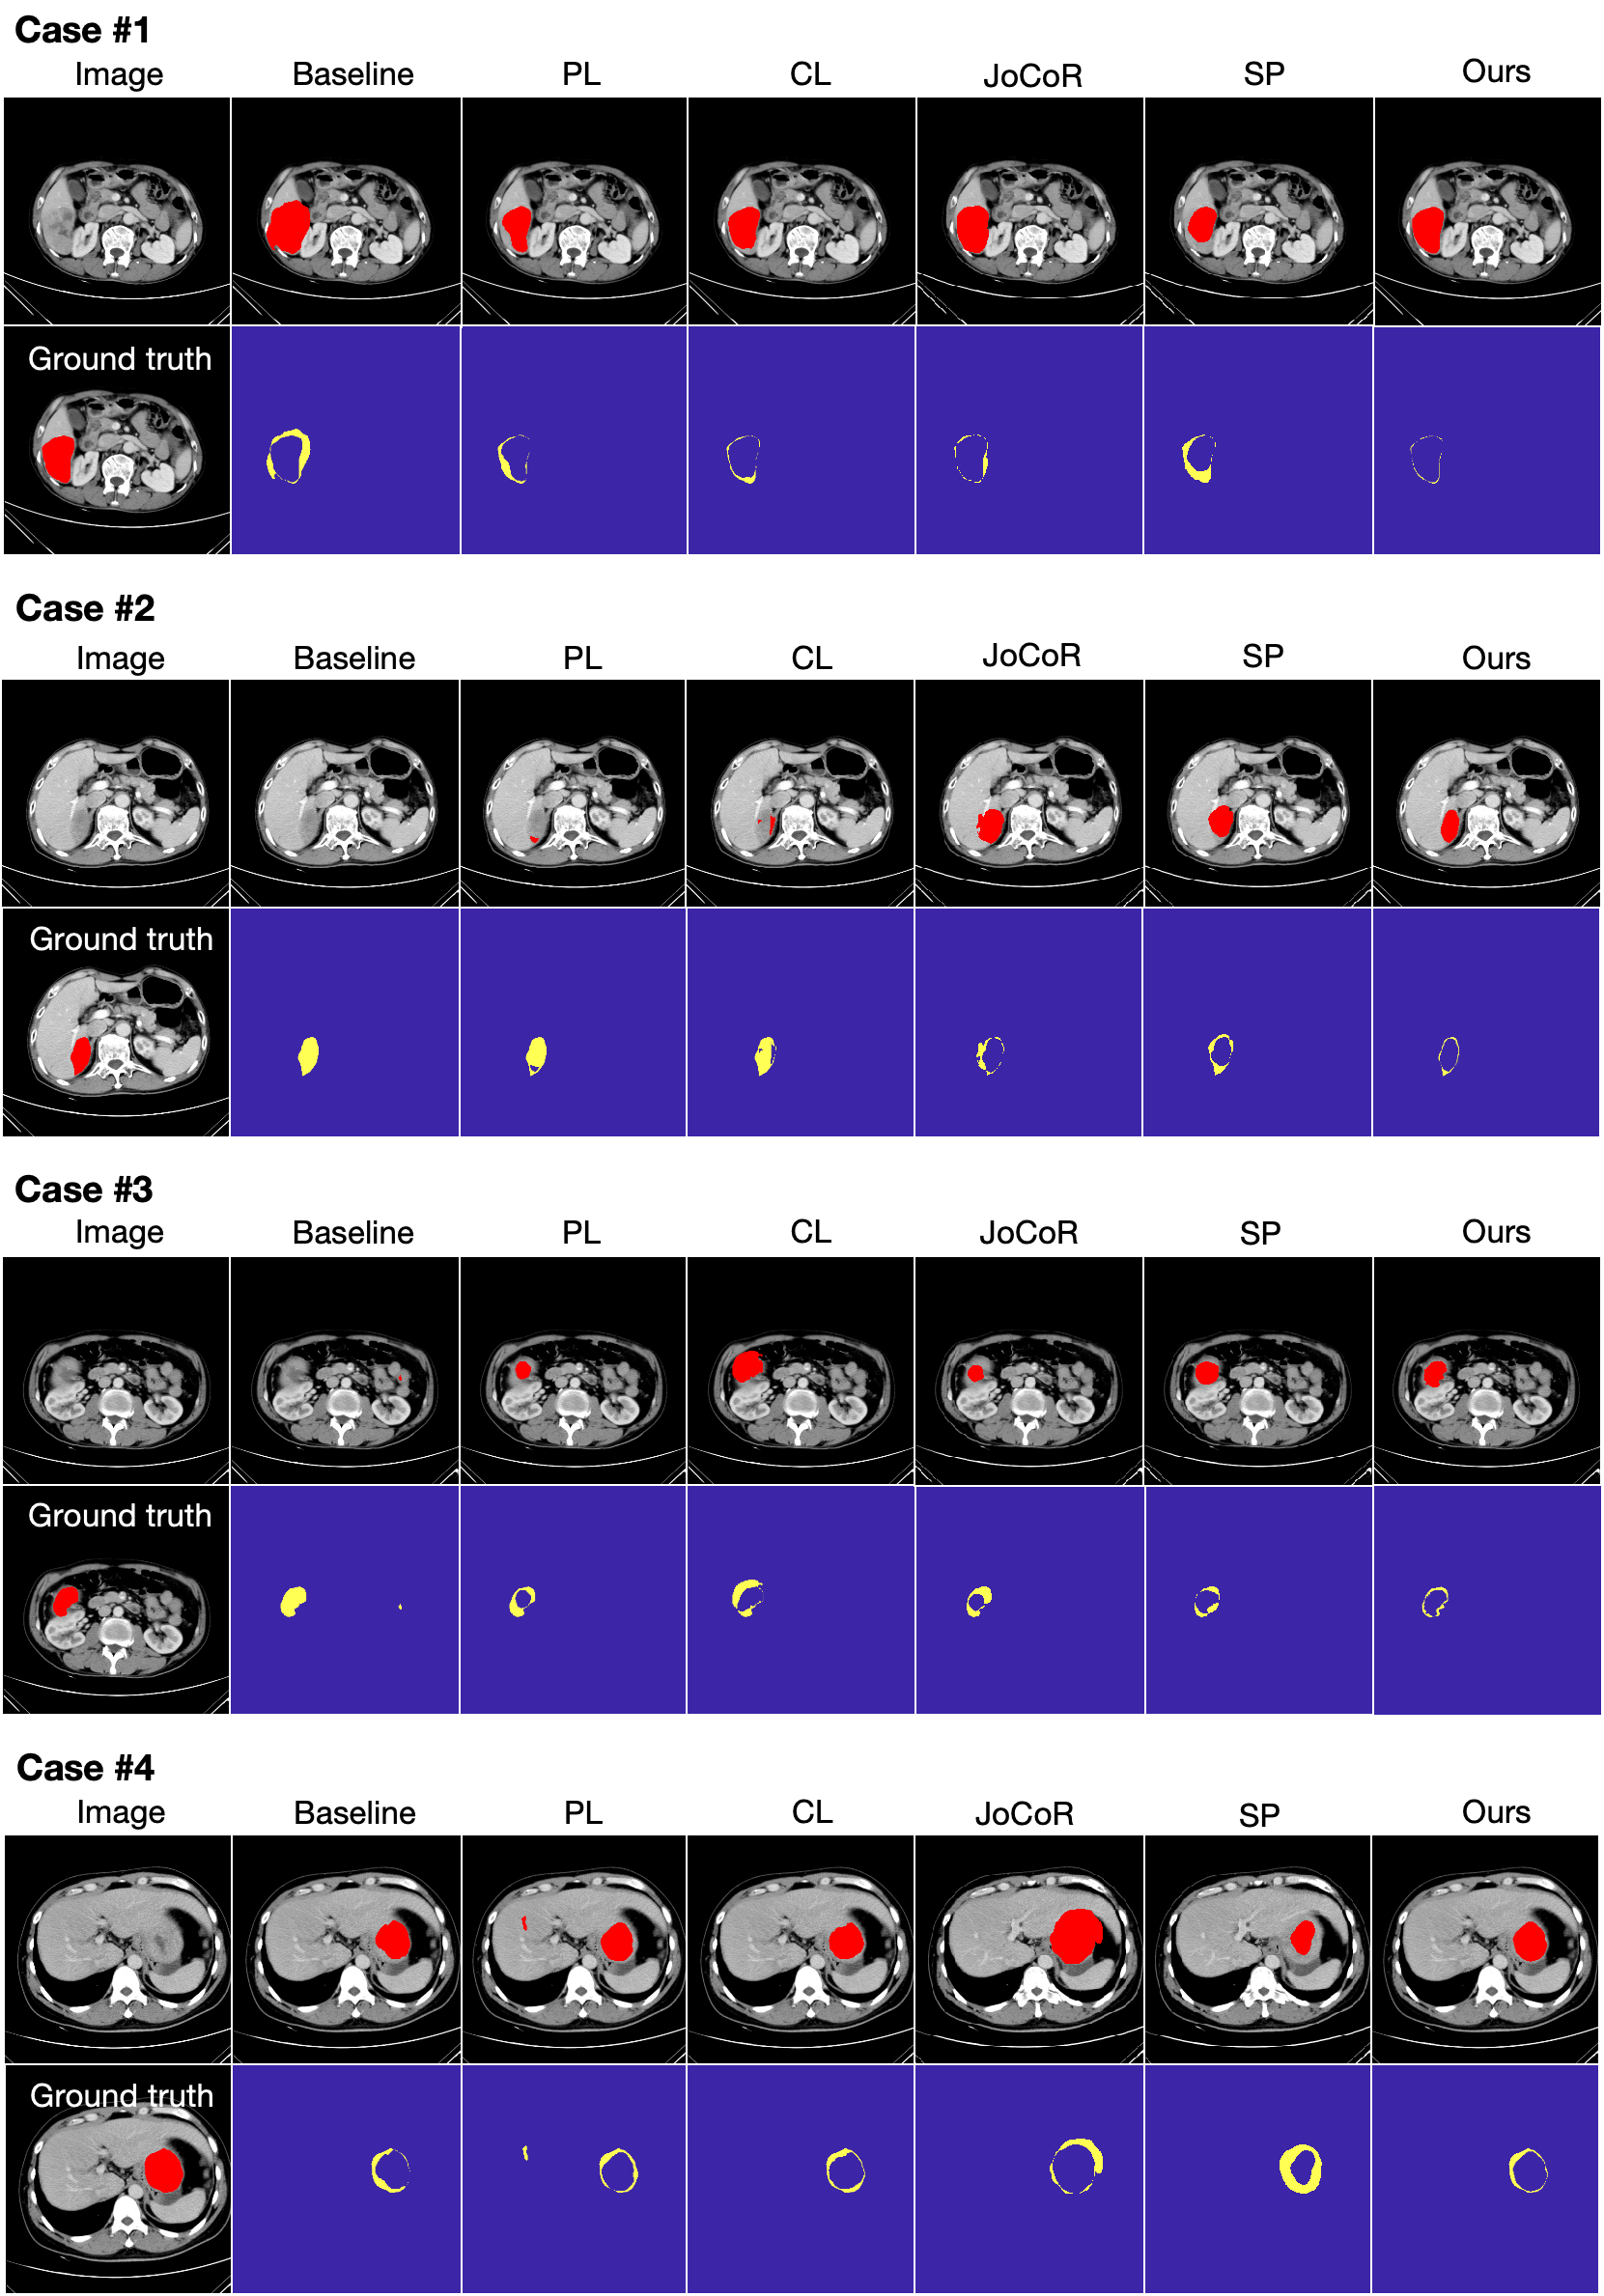

Refer to caption

Figure 5: Qualitative results of different methods on the HCC dataset (B-model, α1=70%subscript𝛼1percent70\alpha_{1}=70\%italic_α start_POSTSUBSCRIPT 1 end_POSTSUBSCRIPT = 70 %, β1=10subscript𝛽110\beta_{1}=10italic_β start_POSTSUBSCRIPT 1 end_POSTSUBSCRIPT = 10), where liver tumor regions are highlighted in red, and discrepancies between network-produced results and ground truths are highlighted in yellow.

In this section, we analyze the comparative experimental results between our method and competing methods on the HCC dataset, both qualitatively and quantitatively. First, we analyze the qualitative results from the visual perspective. Fig. 5 shows several examples of the segmentation results (produced by B-model with α1=70%subscript𝛼1percent70\alpha_{1}=70\%italic_α start_POSTSUBSCRIPT 1 end_POSTSUBSCRIPT = 70 %, β1=10subscript𝛽110\beta_{1}=10italic_β start_POSTSUBSCRIPT 1 end_POSTSUBSCRIPT = 10), where difference maps highlight the discrepancies between network-produced results and ground truths. It is evident that the Baseline network is significantly impacted by noisy samples, leading to obvious false negatives (e.g., Case #2 and Case #3). While the four competing methods exhibit some noise-resistance ability, there still remains a notable gap between their segmentation results and the ground truths. The issue with PL is that it addresses only image-level label noise by reducing the influence of noisy samples but fails to account for disturbances from local noisy regions within each sample. In contrast, the three pixel-level methods (CL, JoCoR, SP) identify pixel-level noise within all samples indiscriminately and rectify the training process. These methods may either introduce extra noise into clean labels or lead to decreased network efficiency and stability. Particularly, CL performs label cleansing in a one-shot manner, meaning the generated pseudo-labels are fixed and cannot be further refined as training progresses. In contrast, our method demonstrates superior performance in noise reduction and achieves optimal segmentation results. By combining the advantages of both image-level and pixel-level methods, our approach preserves clean samples while effectively cleansing noisy ones during training. Furthermore, our method is an iterative method that updates pseudo-labels to reduce noise throughout the training process. As training progresses, these pseudo-labels are continuously refined, enabling the network to better learn robust target features.